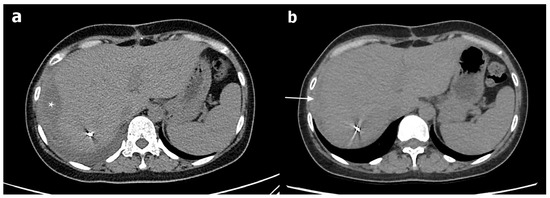

2. Case Presentation